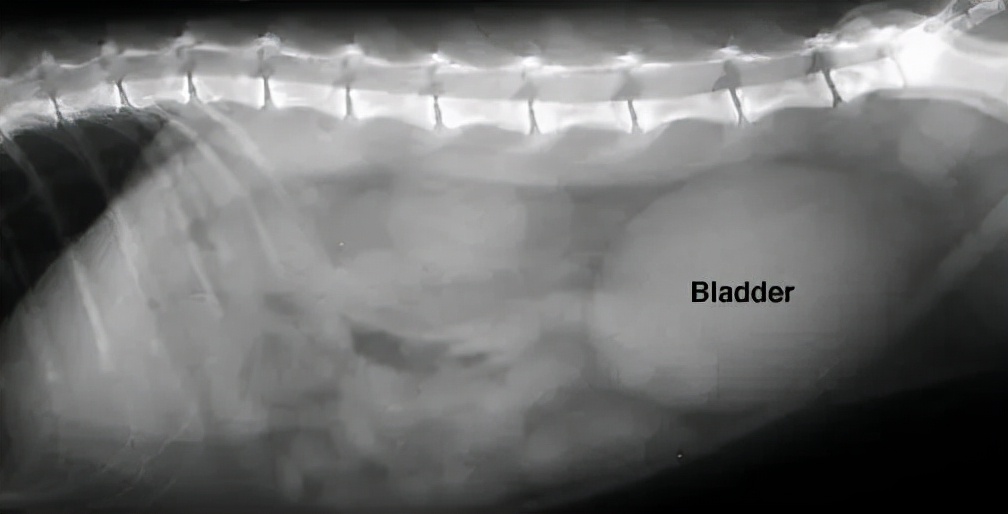

到医院后,兽医一般会触诊腹部,看膀胱是否充盈:对于尿道阻塞的宠物,可以摸到一个大而结实的膀胱,而且无法通过人工挤压膀胱进行排尿。

通常建议进行血液学检查(血常规、血液生化)和尿液检查,来帮助寻找尿道阻塞的原因,而X线和B超能帮我们判断是否有尿结石、尿结晶或尿道栓子。

↑图片右侧的的椭圆形影像是一个充盈的膀胱